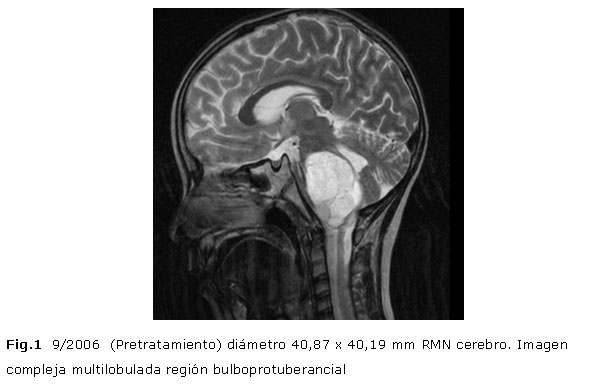

Resonancia Magnética Nuclear (RMN) del cerebro: Imagen compleja hiperintensa, multilobulada en región bulboprotuberancial con diámetro de 40,87 x 40,19 mm. (Fig.1)

Se evalúa la respuesta 6 meses después del tratamiento encontrándose en imágenes de RMN una reducción de aproximadamente 30% de volumen tumoral inicial (Fig. 2) con mejoría clínica evidente (desaparece la cefalea, las nauseas, los vómitos y la alimentación ya se realiza por vía oral, con el cierre de la gastrostomía) reducción de la dosis de esteroides a 25% de dosis inicial. Las reevaluaciones realizadas después del primero y segundo año de tratamiento muestran reducción tumoral de 46 y 70,8% respectivamente (Fig. 3 y Fig. 4) clínicamente asintomático, ya sin tratamiento de esteroides e incorporado a una vida normal.